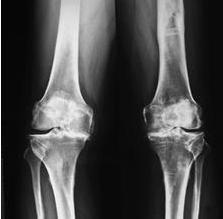

骨性关节炎是人工关节置换术的首选适应症,其他依次为骨无菌性坏死(股骨头坏死)、某些髋部骨折(如股骨颈骨折)、类风湿性关节炎、创伤性关节炎、良性和恶性骨肿瘤、强直性脊柱炎等,只要有关节破坏的X线征象,...